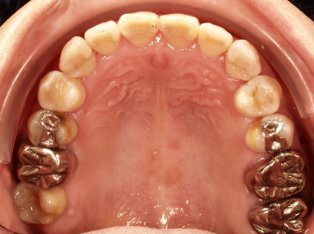

治療前

治療終了前